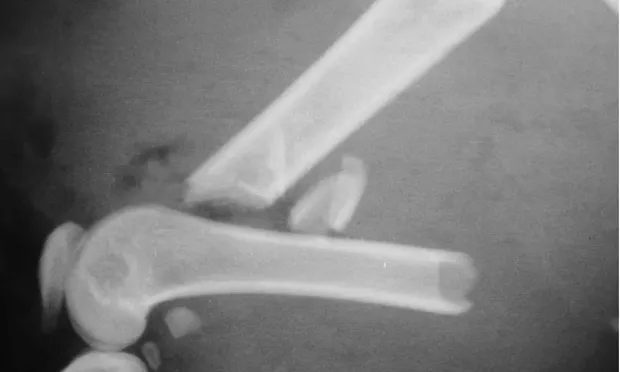

Fractures managed using interlocking nails and biologic technique develop extensive bridging callus and early return to function. A minimally invasive surgical approach (note the surgical skin staples) was made to this fracture to minimize disruption of the blood supply to the bone fragment. The fracture fragments quickly become incorporated in the callus if soft tissue attachments can be maintained.

Healing of the comminuted tibial fracture shown in Figures 2A and 2B after stabilization using an interlocking nail system. This fracture reached bony union in 8 weeks.